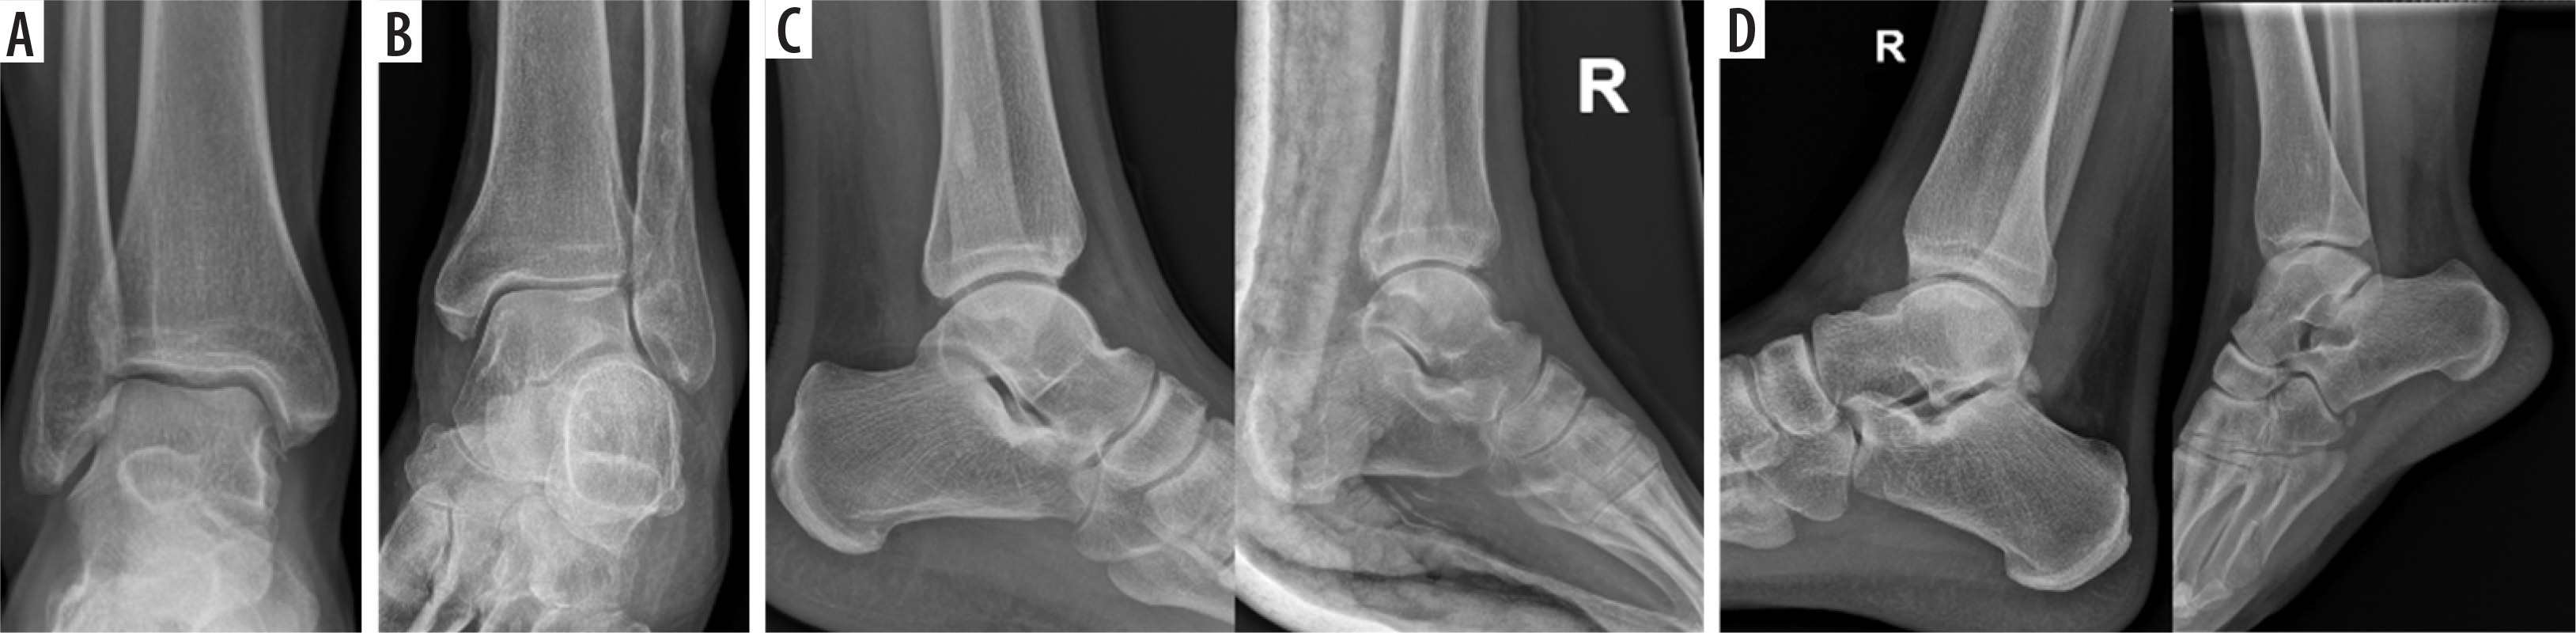

The other projection group consisted of two LAT projections. The LAT projection shows the distal 1/3 of the fibula and tibia bones, the LAT aspects of the talus bone, the calcaneus bone, the other tarsal bones, and the base of the fifth metatarsal bone. The foot should not be rotated in the vertical or horizontal axis, and the fibula bone should overlay the posterior half of the tibia bone. The most important difference between the standard LAT projection and the LATr projection is the presence of evident rotation in the form of the crossing of the arcs of the talus bone and/or the articular surface of the tibia bone in the shape of the letter “X”. It is worth noting that the slightly non-overlapping AJ joint surfaces which are approximately parallel or slightly shifted in the shape of “<” did not affect the angular measurements, and therefore the radiologist included them in the LAT group. The examples of projections assigned to the four groups AP, APr, LAT, and LATr are presented in Figure 1.

Figure 1

Projections of the antero-posterior (AP), rotated AP (APr), lateral (LAT), and rotated LA (LATr) groups. A) AP projection, without a visible tibiofibular syndesmosis gap. B) Oblique antero-posterior projection (APr), showing a clear tibiofibular syndesmosis gap and overlapping shadows of the medial malleolus with a straight line of the medial articular surface of the upper ankle joint. C) Two examples of correct LAT projections, with a slight horizontal axis deviation that does not affect angular measurements. D) Two examples of LATr, with the first image showing the crossing of the articular surface of the talus bone in an “X” shape, and the second image displaying significant horizontal axis rotation, creating a wide fan-shaped appearance resembling “<”